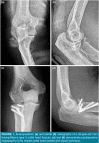

Patients and methods: Between January 2012 and December 2019, a total of 27 patients (16 males, 11 females; median age: 43.2 years; range, 20 to 68 years) with Mason type 3 radial head fractures were retrospectively analyzed. The patients were divided into two groups according to fixation method used. Group 1 consisted of 12 patients who were treated with tripod technique, and Group 2 consisted of 15 patients who were treated with locked plate fixation. Operation time, follow-up period, length of hospital stay, union time, Disabilities of Arm, Shoulder and Hand (DASH) scores, range of motions and complications were recorded.

Conclusion: Our study results demonstrate that comparable results can be achieved in both techniques regarding functional outcome and range of motion. With a shorter union time and less complication rates, the tripod technique should be considered as the primary treatment method for the comminuted radial head fractures without a metaphyseal defect.